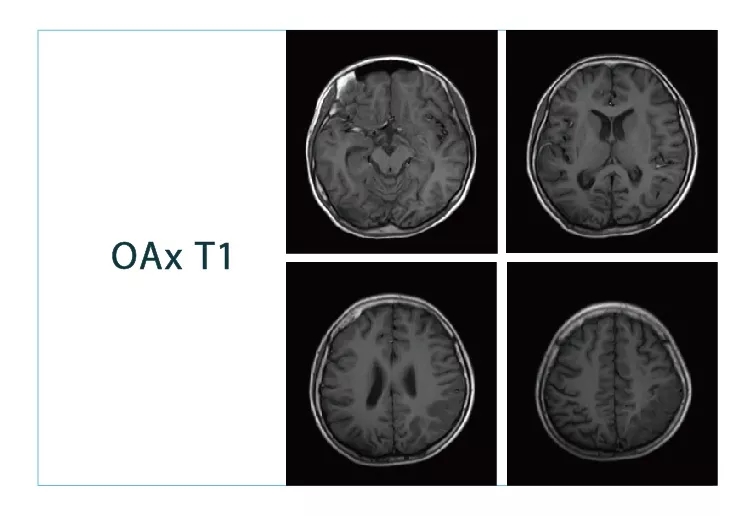

【朗润影像档案】20180817磁共振影像病例结果讨论